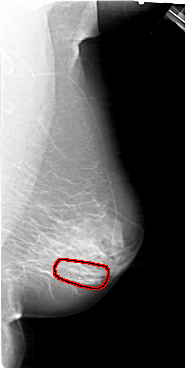

A_1390_1.RIGHT_MLO

RIGHT_MLO LINES 6616 PIXELS_PER_LINE 3331 BITS_PER_PIXEL 12 RESOLUTION 43.5 OVERLAY

FILE: A_1390_1.RIGHT_MLO.OVERLAY

TOTAL_ABNORMALITIES 1

ABNORMALITY 1

LESION_TYPE CALCIFICATION TYPE PLEOMORPHIC DISTRIBUTION LINEAR

ASSESSMENT 4

SUBTLETY 3

PATHOLOGY BENIGN

TOTAL_OUTLINES 1

BOUNDARY